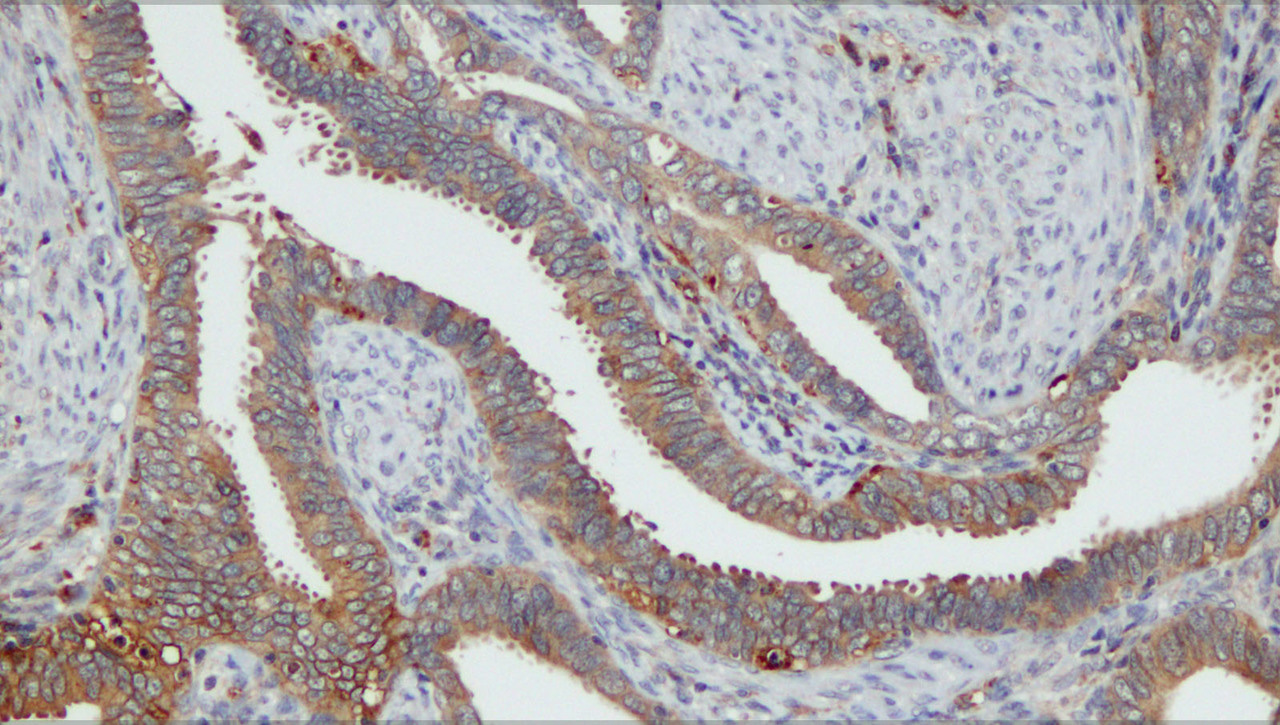

We identified a 10-gene signature with high prognostic value within our Norwegian patient cohort and within the independent cervical cancer TCGA cohort of 304 patients. Within these 10 genes, we investigated the prognostic value of HLA-DQB1 and LIMCH1 by immunohistochemistry (IHC) in over 400 prospectively collected Norwegian cervical cancer patients with complete follow-up. Both proteins had independent prognostic value. Interestingly, by gene expression analyses, we observed that HLA-DQB1high tumours were associated with immune activation and response to Interferon gamma. Correspondingly, by histopathological examination, we observed that these tumours had higher levels of immune infiltrating cells. Tumours with close by and active immune cells are considered good candidates for immunotherapy. To determine the potential of HLA-DQB1 as a marker of immunotherapy response, we investigated the relationship between HLA-DQB1 and PD-L1 expression. Indeed, there was a significant co-expression of HLA-DQB1 and PD-L1. Interestingly, despite other studies4, we did not detect any link between PD-L1 protein expression and cervical cancer survival. When comparing transcriptional profiles of tumours with high versus low PD-L1 protein expression, only a weak link to immune activation in the PD-L1high tumours was detected.

Our study reveals a highly prognostic 10-gene signature, with maintained significance also within an independent patient cohort. Two of the signature genes, HLA-DQB1 and LIMCH1 displayed independent prognostic significance when investigated in a large population-based patient cohort by IHC, indicating a promising role as prognostic biomarkers guiding cervical cancer treatment. HLA-DQB1 was clearly associated with inflammatory reaction, immune activation and immune infiltrating cells. HLA-DQB1 and PD-L1 protein expression was positively correlated, yet PD-L1 was not prognostic within our cohort and was not a strong marker for immune activation. We propose that the prognostic value of PD-L1 in cervical cancer may be ethnicity-dependent, and that HLA-DQB1 should be considered as a marker for response to immunotherapy in cervical cancer.